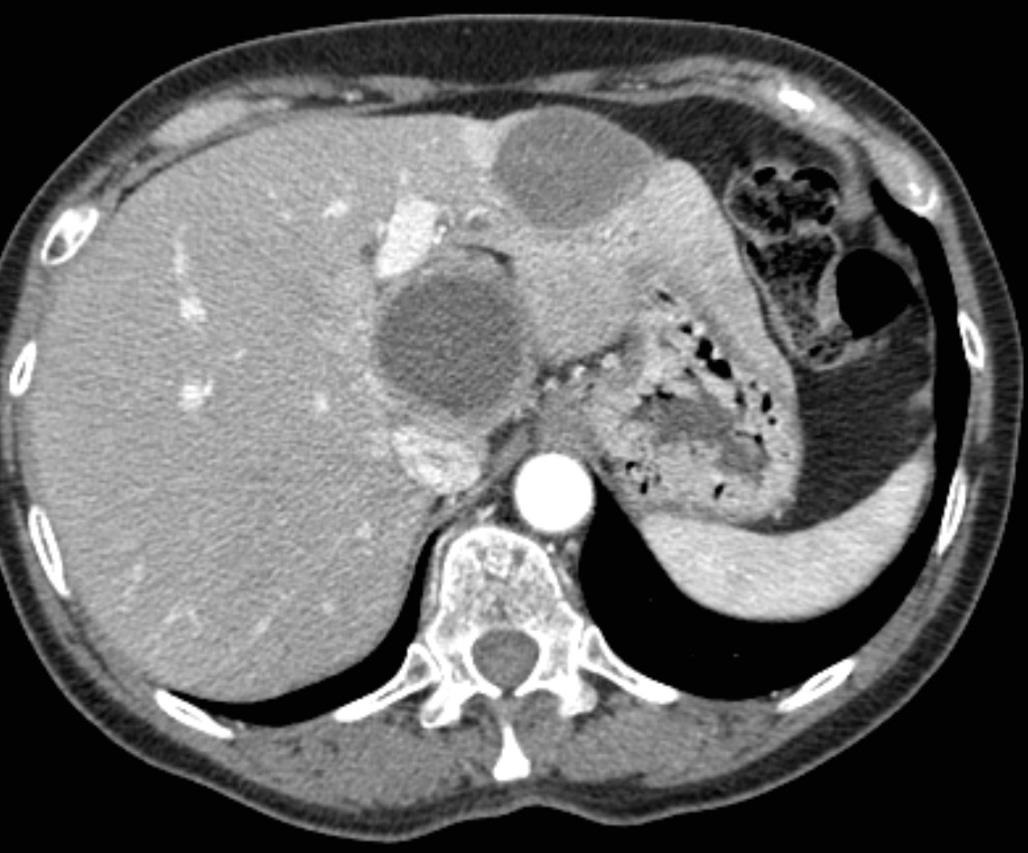

![]() ![]() ![]() ![]() 此图片的顺序待整理(查原文) ![]() ![]() ![]() ![]() Histologically-Proven Efficacy of Bland Embolization in a Patient with Net Liver Metastasis TAE 适应症之三:GIST